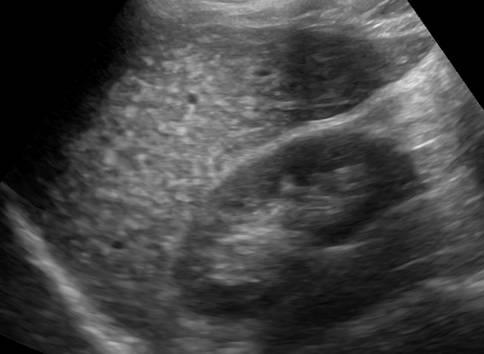

Hamartoma đường mật

» Thông tin: Nam giới – 39 tuổi.

» Lâm sàng: Kiểm tra sức khỏe.